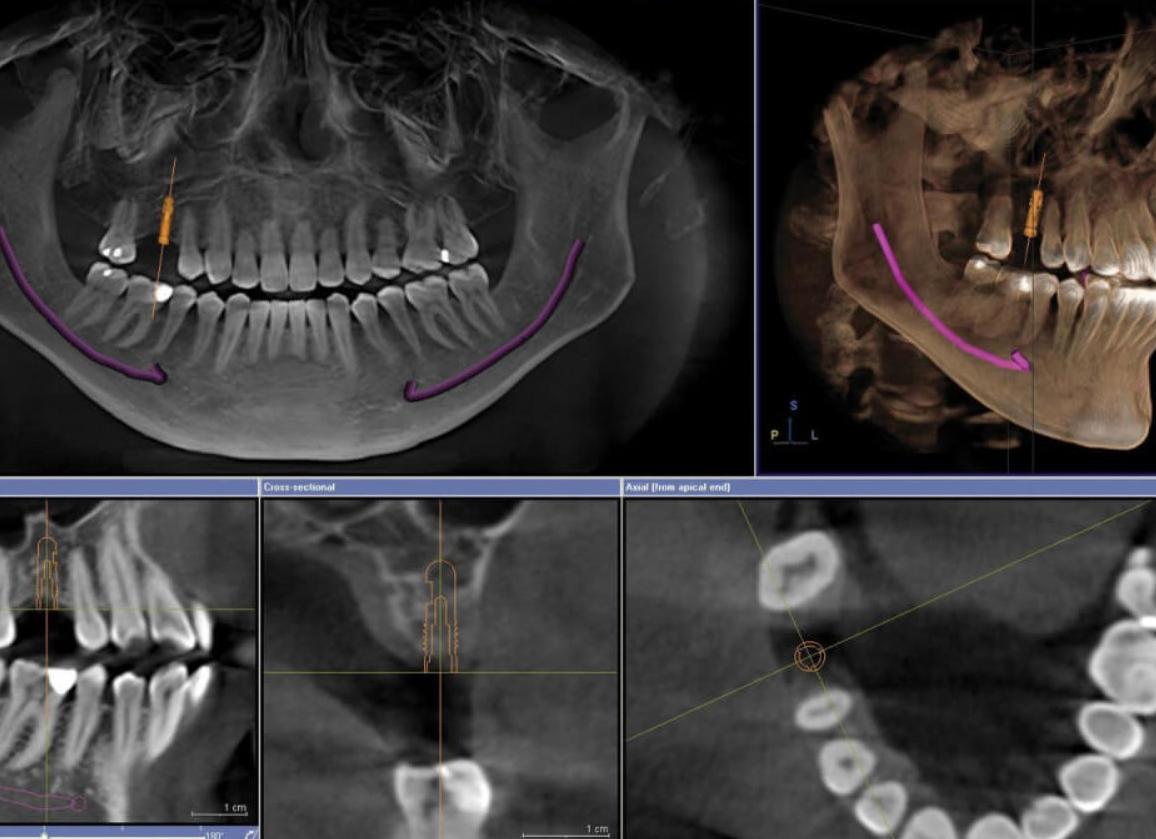

КТ всей челюсти – стандартная томограмма

Луч проходит через очень маленький участок диагностируемой области, и большое количество снимков поступает на компьютер, к которому подключен монитор. Это позволяет создать трехмерное изображение очень высокого разрешения во фронтальной, аксиальной и сагиттальной плоскостях. Программа воспроизводит его через 1–2 минуты после процедуры. Врач может его просмотреть детально по трем осям, послойно, увеличить, перевернуть. Профессионал, расшифровывая полученное изображение, описывает органические образования и структуру внутренних тканей.

Послойные срезы, полученные в результате сканирования вашей челюсти, обрабатываются с помощью компьютера.

Они очищаются от шумовых помех и комбинируются в единое, трехмерное изображение, позволяющее рассмотреть исследуемую область со всех сторон.